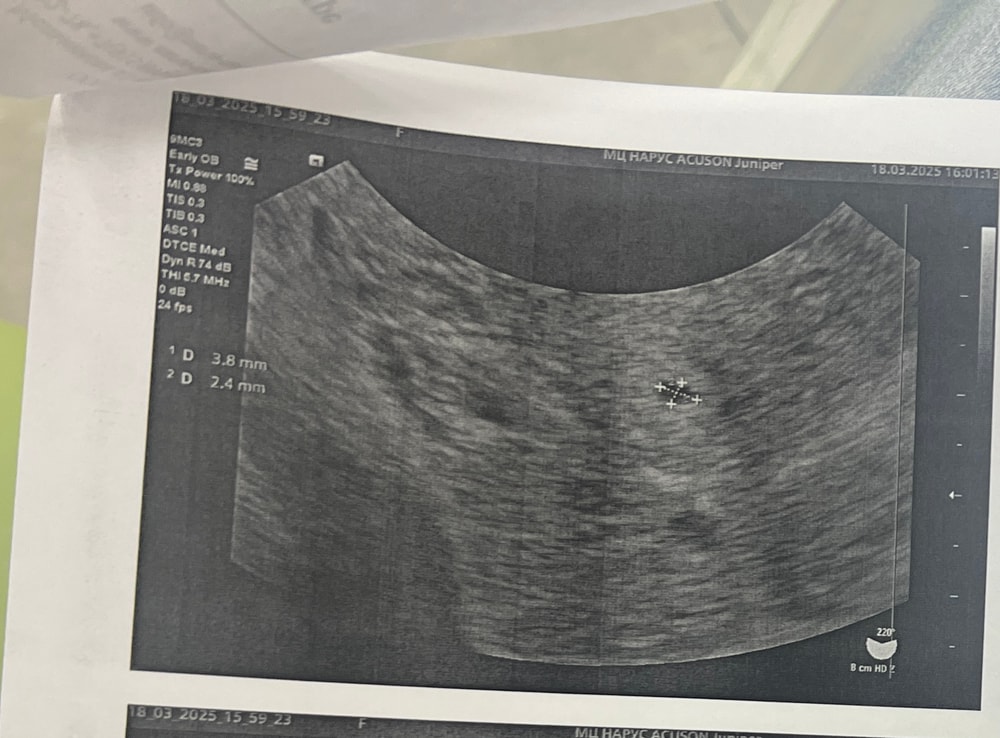

Вчера была на узи - нашла ПЯ 3 мм, совсем мелкое, но я то думала, что ХГЧ хорошо растет и ожидала ПЯ побольше, а ХГЧ там тормознулся видимо. По месячным 5+3 нед. Это все? Такая динамика не сулит ничего успешного?

Хгч неплохой, пя маловат, но это может быть банально особенности аппарата узи. У меня в один день на хреновом узи был 6мм, а на другом 11. Разница аппаратов

Наталья, я ходила в платные хорошие клиники. Вот вам для примера два узи, на обоих дала 9/03. На первом сказали яйца пустые, на втором узи врач уже видела мешочек. Второй ПЯ у меня был поменьше, но тоже развился эмбрион и все хорошо

Да и пя у вас на совсем чуть отстает. Должно быть около 7 мм